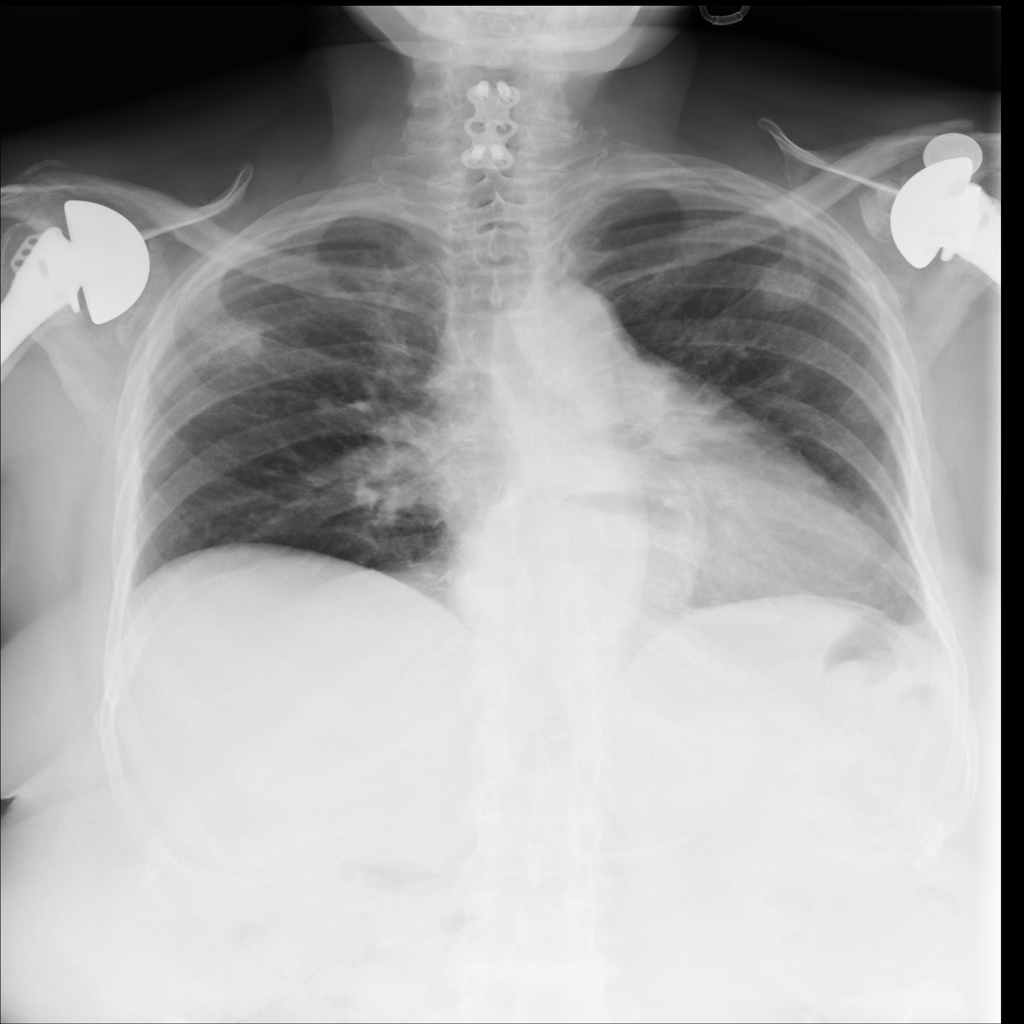

PAT-4F7E · IMG-000Hernia

PAT-4F7E · IMG-000

PA